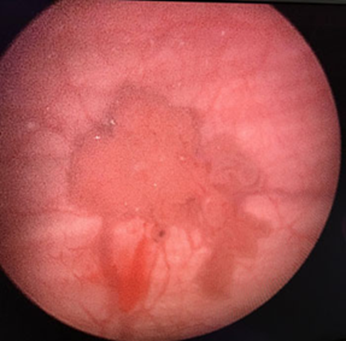

- Cystoscopy: – this procedure allows Uro Onco surgeon,to look inside the bladder by inserting Cystoscope through the urethra into the bladder.

- Bladder biopsy: – this is the most comprehensive test to see if you have bladder cancer. TThrough cystoscopy Uro-Onco takes a adequate piece of the bladder tissue for histopathology examination.

- Transurethral Resection of a Bladder Tumour (TURBT) –Cancerous bladder tissue is removed through the urethraSubsequently, chemotherapy or immunotherapy can be directly given inside the bladder through urinary catheter.